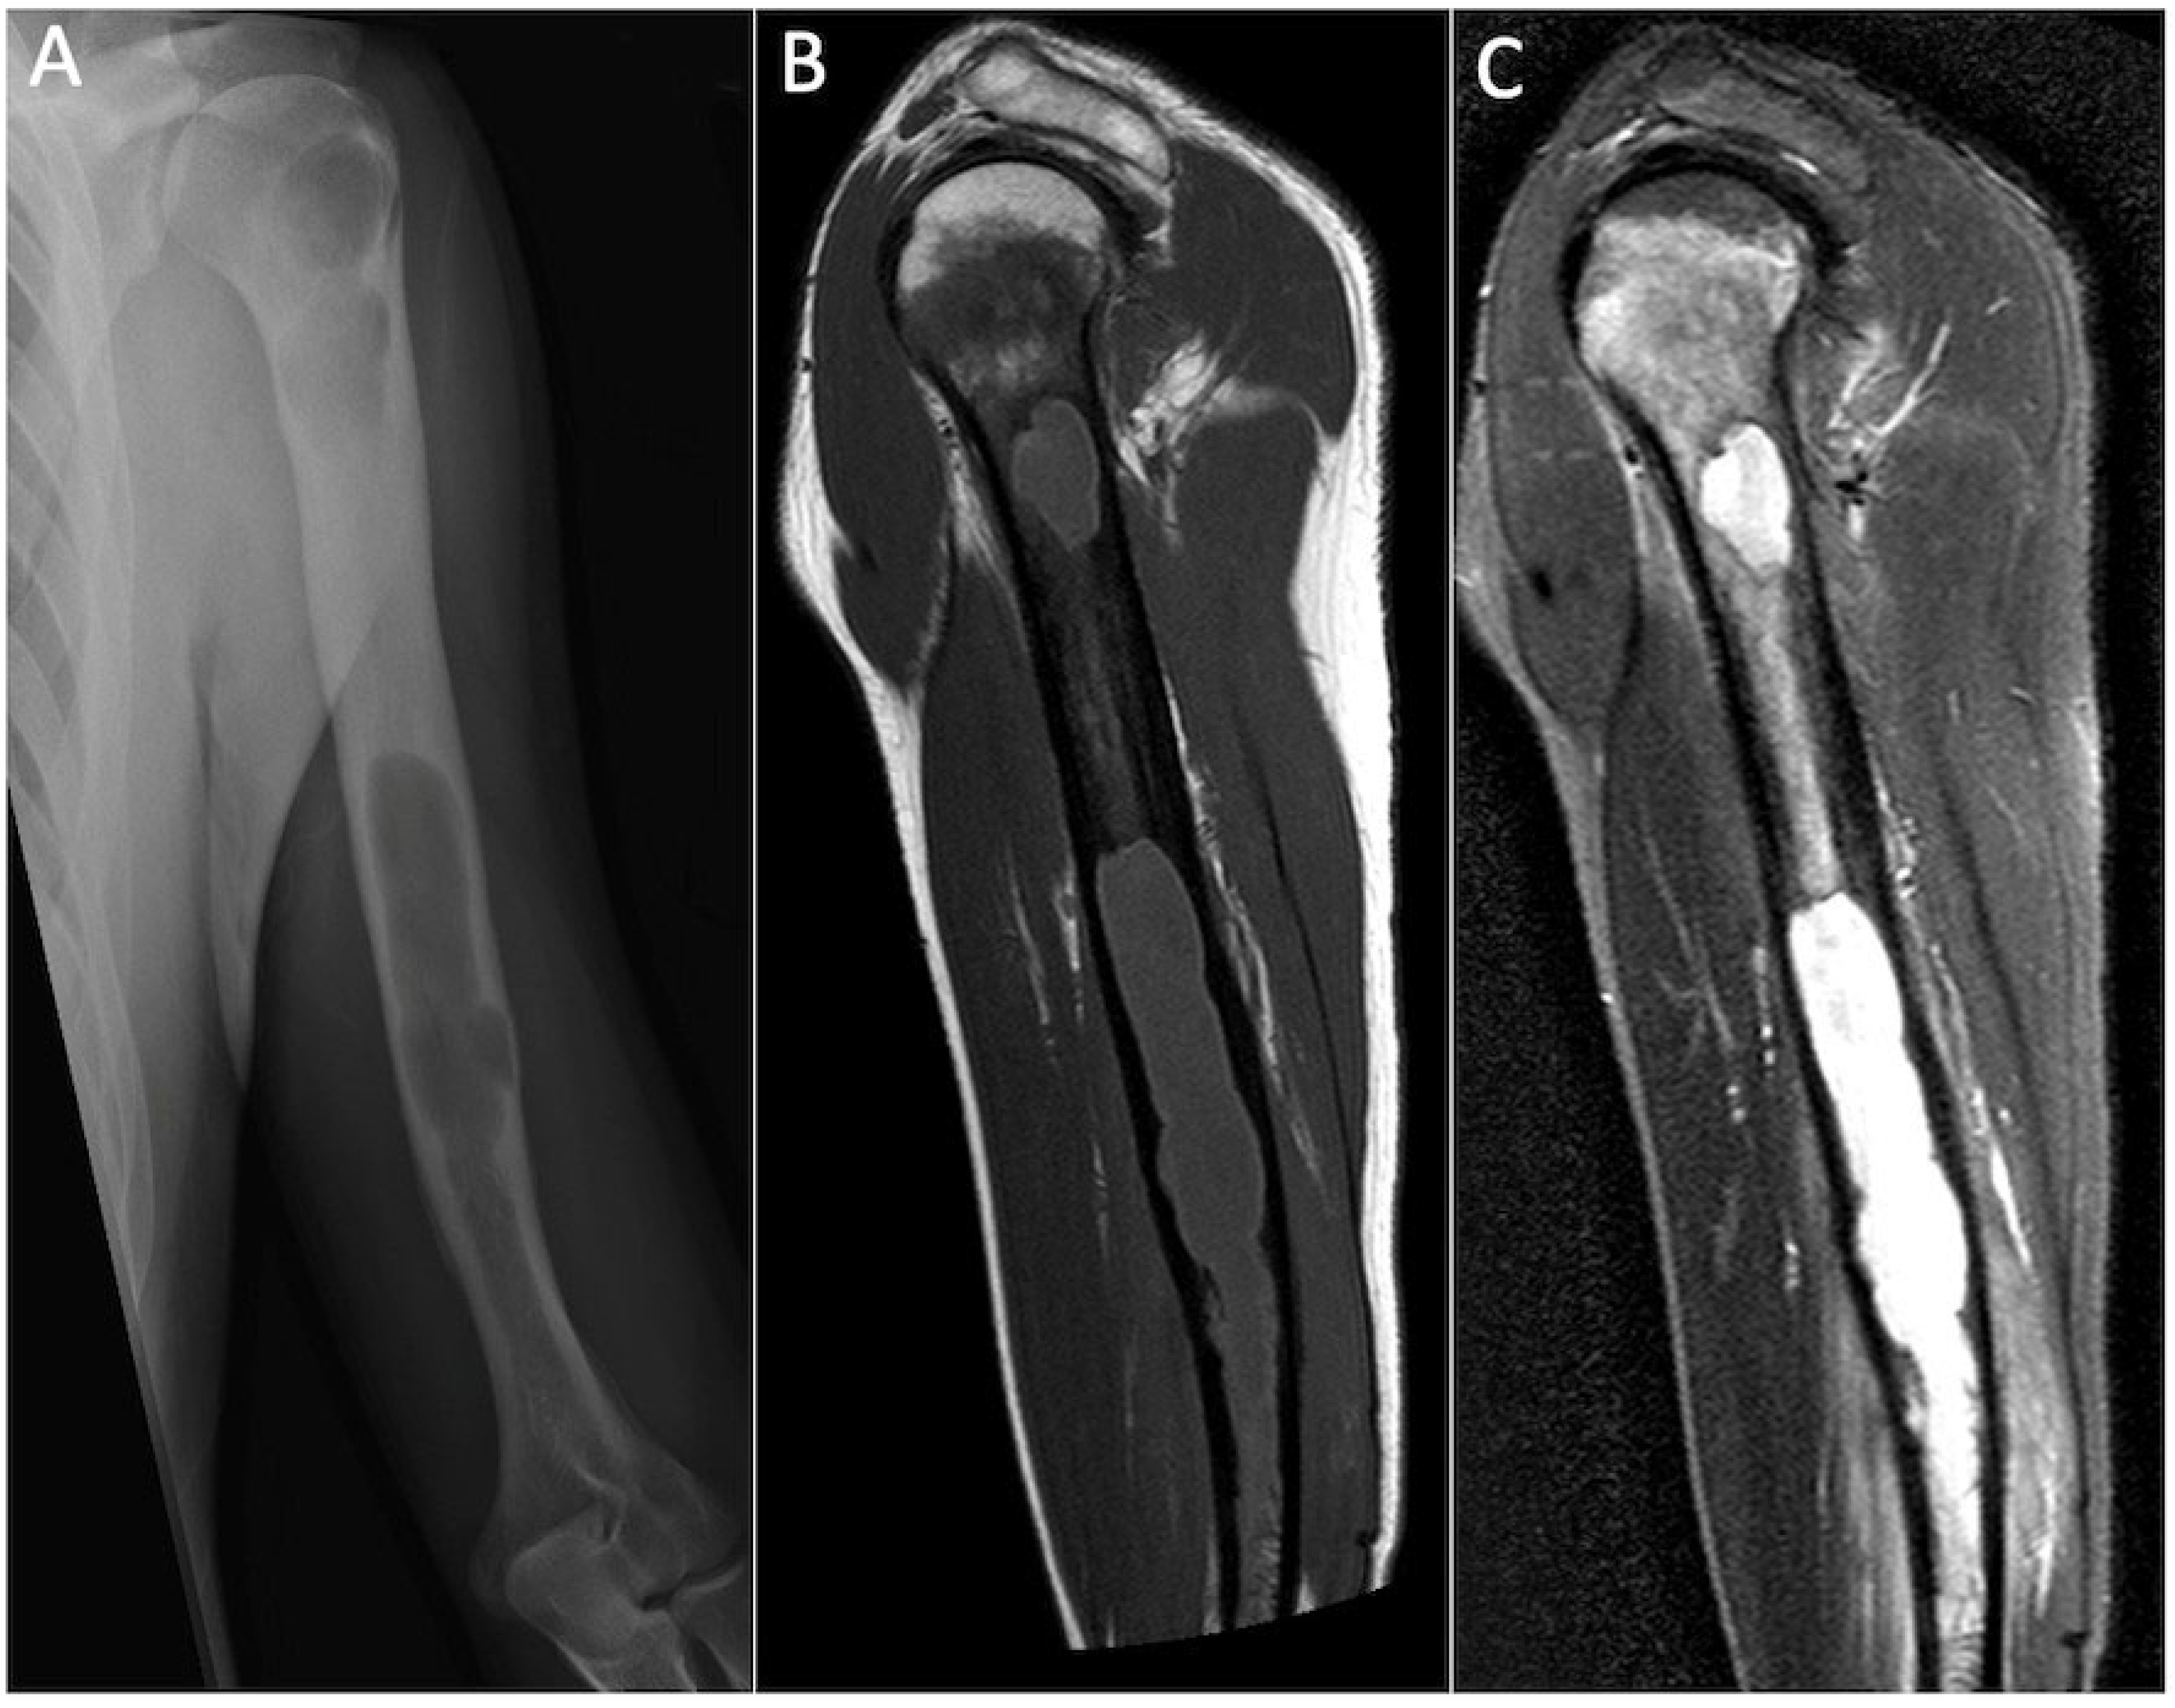

5.1. Chondroblastoma